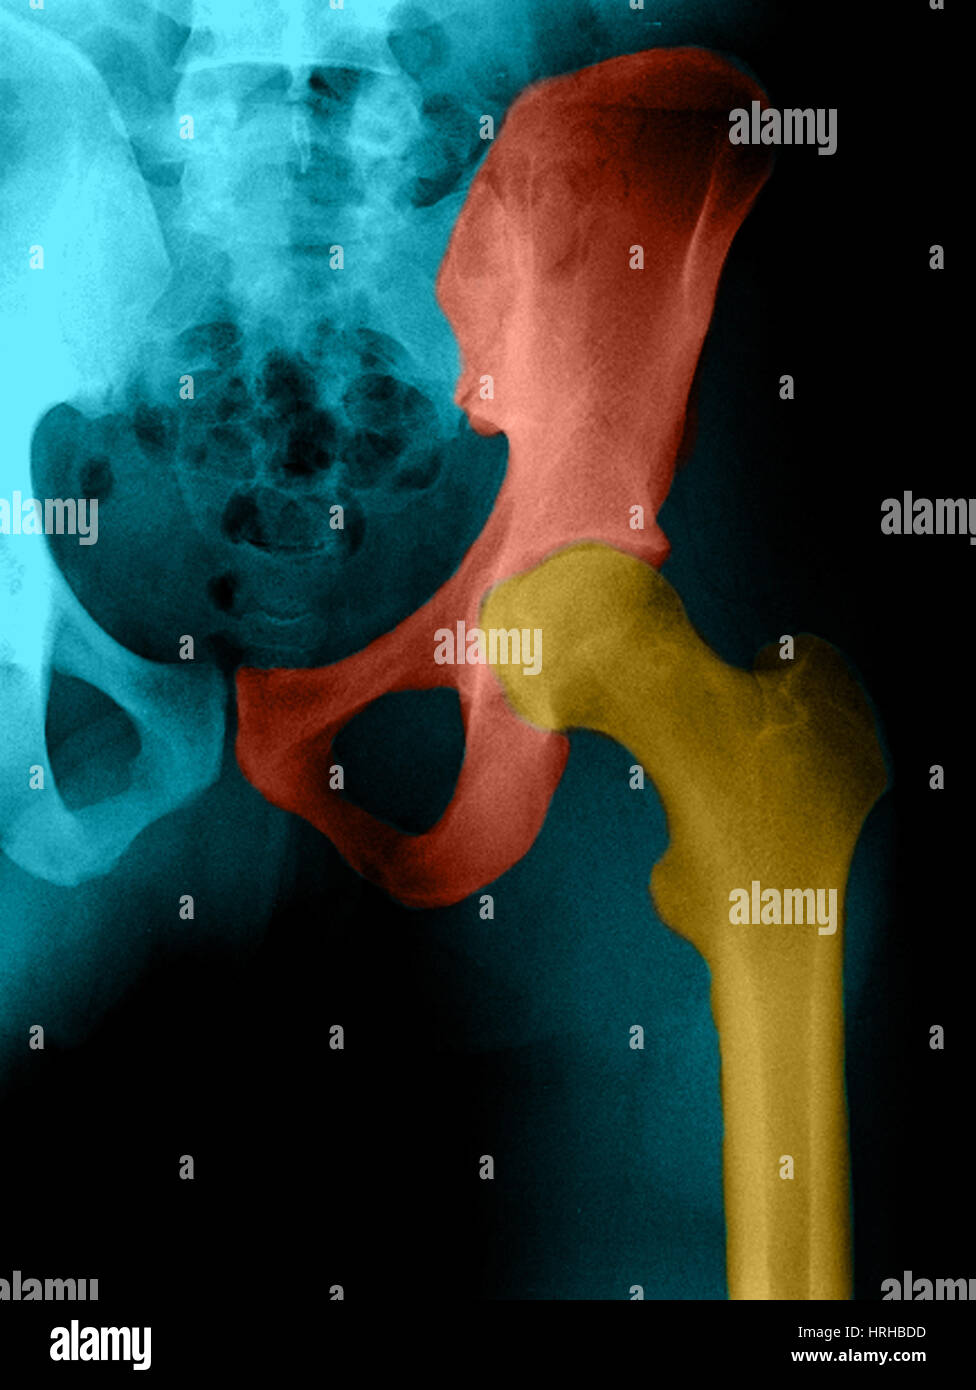

From www.sciencephoto.com

Female pelvis bones and joints, Xray Stock Image C033/7354 Science Types Of Hip X Ray Views    imaging of the pelvis can be required following minor or major trauma and for nontraumatic painful conditions.   radiographic protocols designed for the hip can vary based on the clinical scenario and personal preference of the referring physician.   the hip series is comprised of an anteroposterior (ap) and lateral radiograph of the hip joint.  the hip series. Types Of Hip X Ray Views.